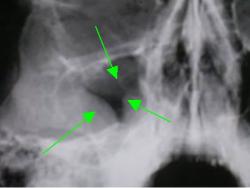

Название случая. «Хронический правосторонний гайморит, с наличием полипоподобных образований в левой гайморовой полости».

Протокол. Полученное изображение (1) обработано в цифровом формате (эквилизация, увеличение, анализ в условиях «негативного изображения»). Справа определяется резкое объёмное уменьшение правой гайморовой полости (2) за счет резкой пристеночной (подушкообразной) гиперплазии слизистой оболочки. Снижение прозрачности средней интенсивности, однородной структуры, с четким выгнутым внутрь пазухи контуром. В левой гайморовой полости, локально в верхнем наружном отделе определяются два полипоподобных образования.